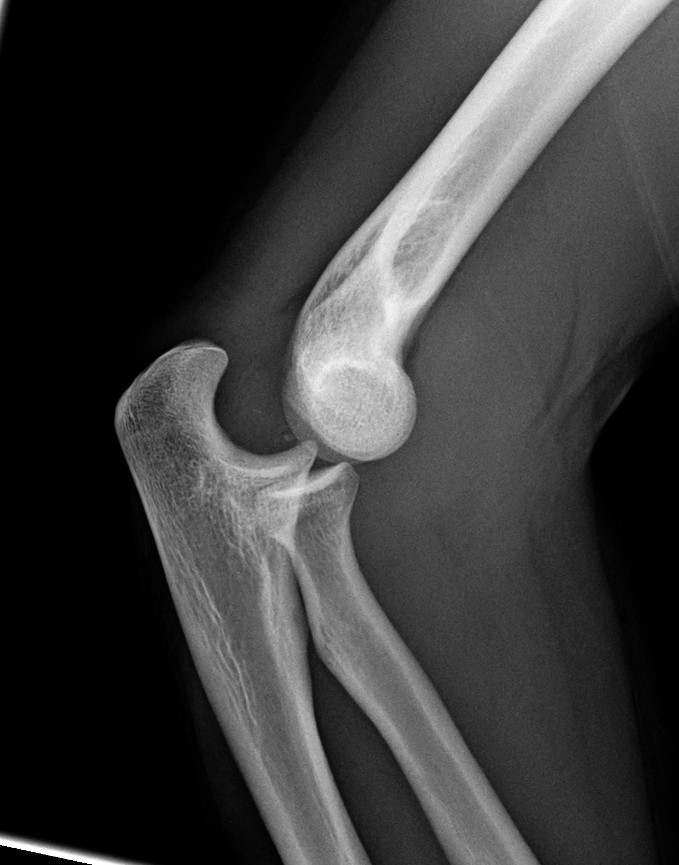

팔꿉관절(주관절)은 상완골, 요골, 척골 사이에 존재하는 관절이다. 굽힘과 폄(굴신)을 행하는 것은 주로 위팔뼈와 척골 사이이다.

팔꿈치 관절은 공통 관절낭으로 둘러싸인 세 개의 다른 부분으로 구성되어 있다. 이들은 상완의 상완골, 전완의 요골와 척골 사이의 관절이다.| 관절 | 에서 | 로 | 설명 |

| 상완척골 관절 | 자뼈의 도르래절흔 | 상완골의 도르래 | 단순한 경첩 관절로 굴곡 및 신전 운동만 가능하다. |

| 상완요골 관절 | 요골 머리 | 상완골의 작은머리 | 볼 소켓 관절이다. |

| 근위 요척 관절 | 요골 머리 | 자뼈의 요골절흔 | 굴곡 또는 신전의 모든 위치에서 요골은 손을 함께 운반하며 회전할 수 있다. 이 움직임에는 손바닥 엎침과 손바닥 뒤침이 포함된다. |

해부학적 자세에서 팔꿈치에는 네 개의 주요 뼈대 랜드마크가 있다. 상완골의 하단에는 몸에 가장 가까운 쪽(내측)과 몸에서 가장 먼 쪽(외측) 표면에 있는 상완골 내측 상과와 상완골 외측 상과가 있다. 세 번째 랜드마크는 자뼈 머리에서 발견되는 주두이다. 이들은 ''Hueter 선''이라고 하는 수평선상에 놓여 있다. 팔꿈치가 굴곡될 때, 이들은 정삼각형과 유사한 ''Hueter 삼각형''이라고 하는 삼각형을 형성한다.[5]